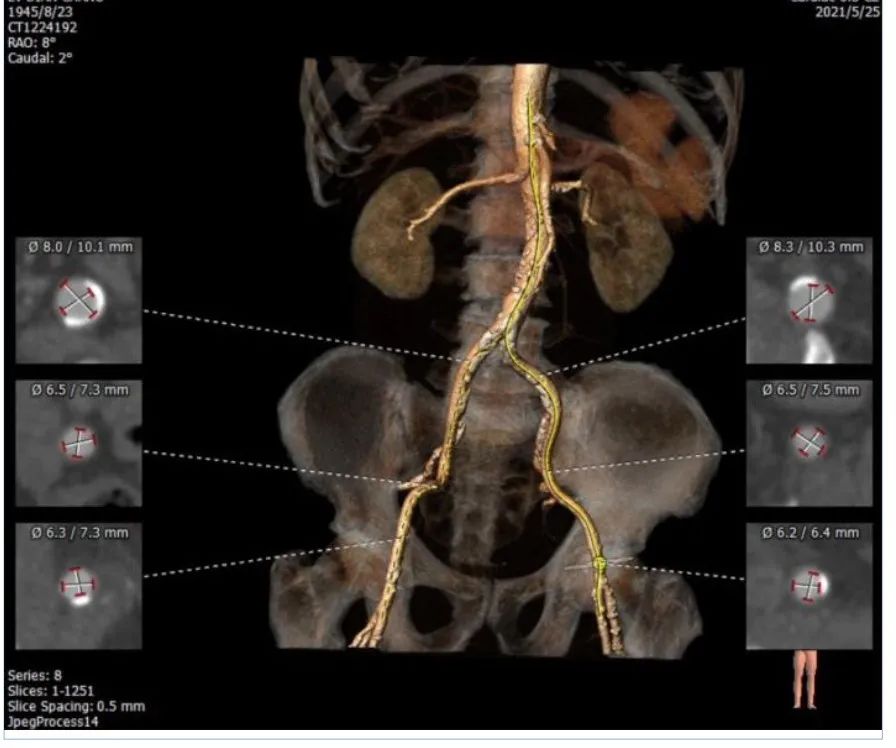

外周血管及主动脉弓解剖:

患者主动脉弓角度、弓距可。双侧入路血管内径可,CT见明显钙化,股动脉分叉位置可,右侧股动脉存在钙化斑块,存在血管损伤风险。

入路血管无严重钙化及其他病变,双侧血管内径良好,整体入路血管条件良好。